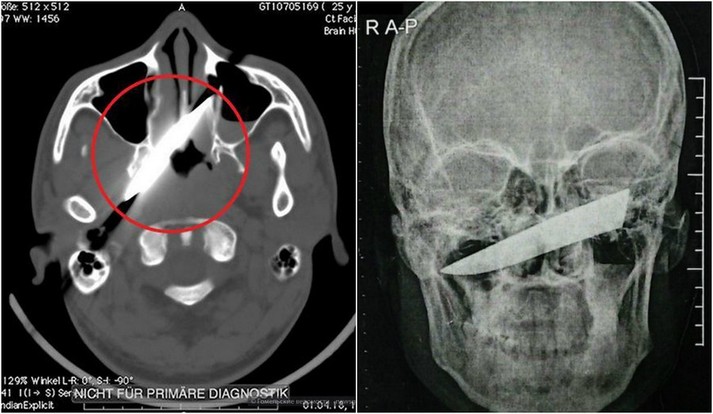

Рентген показал, что нож зашел на 10 см в голову, но не задел ни одной артерии

Удар ножом в глаз он получил во время пьяной драки в баре. После этого пострадавший как ни в чем не бывало отправился домой спать. На следующий день мужчине все же пришлось посетить медучреждение. Лезвия он не заметил, однако голова и глаз очень болели. Рентген показал, что нож зашел на 10 см в голову, но не задел ни одной артерии. Врачи даже решили перенести операцию на четыре дня, пока оформлялись необходимые документы.